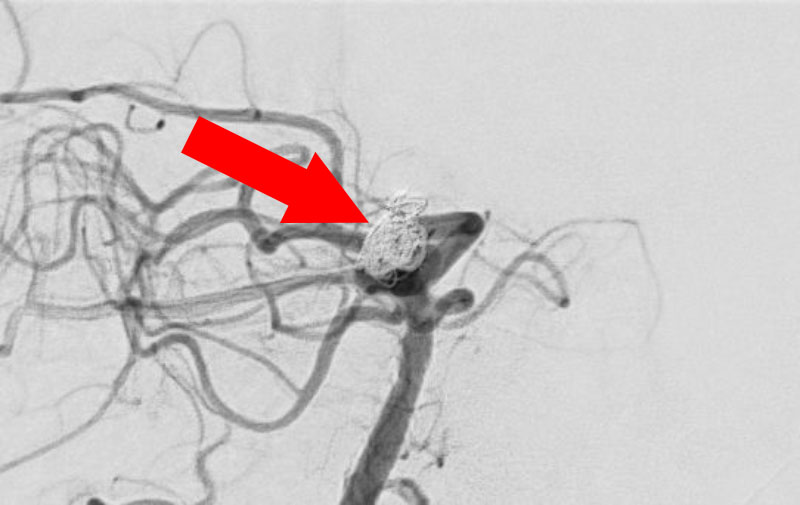

No.1627 手術前

No.1627 手術中

No.1627 手術後